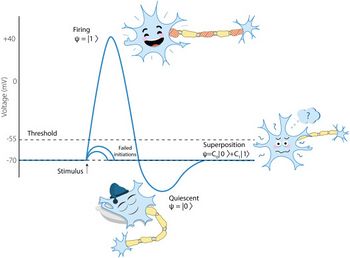

Masticationpedia is a not-for--profit Anglo-Saxon organization, it is a Charity that operates in dental medical research, in particular in the field of neurophysiology of masticatory rehabilitation.

Einstein's metaphor is emblematic: the theory is when we know everything but nothing works. Practice is when everything works but we don't know why. In any case, we always combine theory and practice: nothing works and we don't know why. Basically, this also happens in dentistry where everything doesn't work and we don't know why. Well, Masticationpedia aims to probe the functional properties of the masticatory functions, ranging in various fields of science without prejudices or corporate ideologies to grasp the access key to the system. See video

If shared, this scientific-clinical know-how will be converted into specific 'Centers' that will employ neurophysiological technologies for masticatory rehabilitation called Masticationpedia Network and will be the exclusive brand of each affiliated dentist. See the first Masticationpedia Network